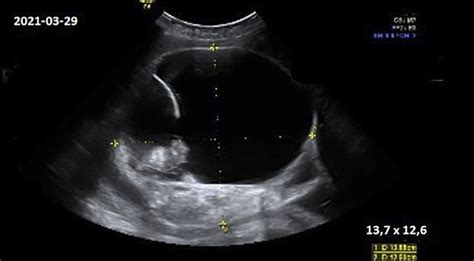

Nėštumą labai patikimai galima nustatyti atlikus kraujo tyrimus. hCG kraujo tyrimas atliekamas ankstyvam nėštumui nustatyti. Tyrimas paprastai atliekamas 6-10 dieną po implantacijos (ji įvyksta maždaug 6-12 dienų po apvaisinimo). Nėštumą galima nustatyti ir atlikus ankstyvąją echoskopiją, t.y. Tiesa, ankstyvoji echoskopija retai atliekama siekiant tiesiog patvirtinti nėštumą.

- Patvirtinamas nėštumas ultragarsu.

11-13 nėštumo savaitė atliekamas detalus ultragarsinis tyrimas. Nustatoma preliminari gimdymo data. Apžiūrimos pagrindinės kūno dalys, smegenų struktūra, ieškoma chromosominėms genetinėms ligoms būdingų žymenų. Bene svarbiausias rodmuo - vadinamosios sprando raukšlės (kitaip - vaiskumo) matmuo.